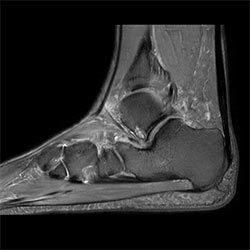

In a society where reimbursements are declining and chronic conditions lead to increased MR procedures and longer waiting times, there is ever increasing pressure on the radiology department. Today, further attempts to accelerate, compromise image quality or are limited to a narrow range of scans. Therefore, to meet the increased demand for productivity, a technology break-through in acceleration is still required. Leveraging our long standing leadership position in speed (i.e. SENSE), Philips brings compressed SENSE, a breakthrough in productivity.

Our goal is to reduce scan time, but we want the same image quality as before”

Sabine Sartoretti, MD, Head of Neuroradiology, Institute of Radiology and Nuclear Medicine, Kantonsspital Winterthur, Switzerland

Learn more about the main principles of Compressed SENSE and how it introduces a paradigm shift in productivity, how Compressed SENSE was designed around image quality, and how it advances productivity for clinical MR imaging.

Read about the experiences from Kantonsspital Winterthur (Switzerland) who experienced Compressed SENSE to be a simple yet powerful way to accelerate MRI scanning for different contrast types and sequences, in 2D as well as 3D.